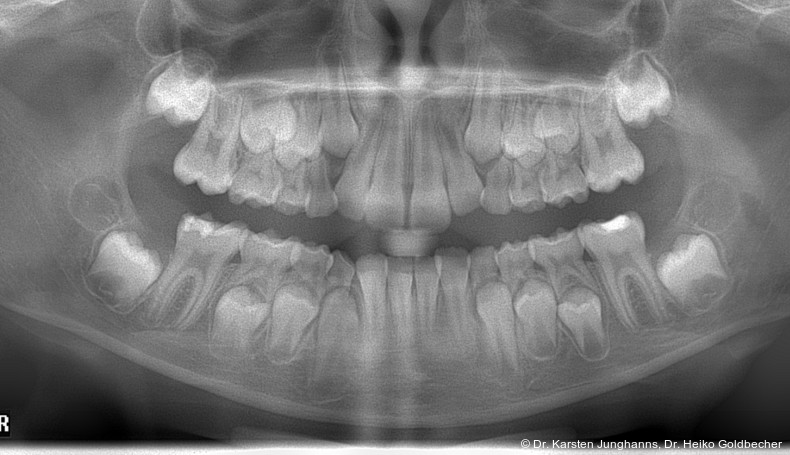

Eine Patientin stellte sich im Alter von neun Jahren erstmals vor. An den ersten Molaren des Unterkiefers wurden vom Hauzahnarzt eine MIH diagnostiziert (Abb. 1a) und die Zähne als nicht erhaltungsfähig eingestuft. Die beiden ersten Molaren wurden hemiseziert und der distale Anteil extrahiert. Gut zu erkennen ist auf dem OPG die annähernd achsengerechte Mesialisierung der zweiten Molaren sowie die Aufwanderung der Zahnkeime der dritten Molaren (Abb 1b: ca. 1,5 Jahre nach Hemisektion). Noch vor Durchbruch der zweiten Molaren in die Mundhöhle wurde auch der mesiale Anteil entfernt. Der spontane Lückenschluss erfolgte innerhalb der nächsten anderthalb Jahre (Abb. 1c). Die endgültige Achsstellung kann nach Ausdehnung der Teilmultibandapparatur eingestellt werden.

Auch wenn nach dem Minimalschadensprinzip meist der Zahnerhalt anzustreben ist, können die Begleitumstände eine Extraktion rechtfertigen. Der Hauszahnarzt übernimmt in der Regel eine Schlüsselrolle im Entscheidungsprozess und der möglichen Einbeziehung von Fachzahnärzten. Erfahrungsgemäß treten insbesondere im Unterkiefer Komplikationen in Form von Alveolenkollaps und der sich daraus entwickelnden Nebenwirkungen auf, welche es zu vermeiden oder zu verhindern gilt. Bei der Indikation zur Extraktion eines Unterkiefermolars sollte eine Hemisektion in Erwägung gezogen werden. So kann mit wenig Aufwand ein achsengerechter Spontandurchbruch der zweiten und dritten Molaren erreicht werden. Sollte die Entscheidung zu einem späteren Zeitpunkt getroffen werden, kann auch hier durch eine Mesialisationsmechanik (Abb. 2c) eine körperliche und achsengerechte Einstellung erreicht werden. Gut zu erkennen ist in Abbildung 2, dass der dezente frontale Engstand weiterhin besteht und keine Distalisierung der Frontzähne oder Prämolaren stattgefunden hat. Spätere Extraktionen mit Komplikationen können vermieden werden. Bisher hat diese Indikation zur Hemisektion (MIH) noch keinen Eingang in den Bema gefunden. In Hinblick auf ein verbessertes Lückenmanagement mit geringeren Risiken, verkürzten Behandlungszeiten, geringerem apparativen und finanziellen Aufwand sollte eine Anpassung zukünftig diskutiert werden. Falls der dritte Molar angelegt ist, wird in vielen Fällen ein Lückenschluss mit Einordnung der zweiten und dritten Molaren möglich sein, sodass am Behandlungsende ein adultes Gebiss mit 28 gesunden Zähnen vorliegt.